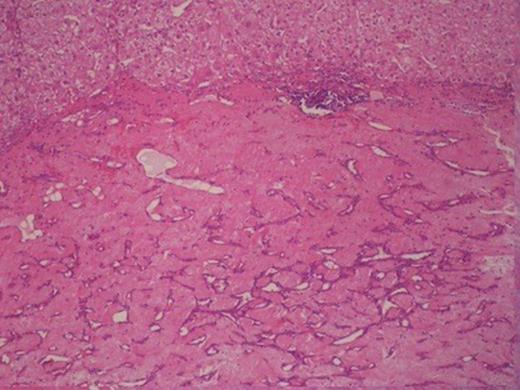

Histologically, the tumour was composed of fibroblasts that were arranged vertically. Smooth muscle cells were also recognized that apparently were remnants of the mucosal muscle layer. Also, redundant confluent lymphocytes, plasmocytes, mast cells with rare giant cell forms, as well as redundant eosinophilic granulocytes were recognized. The supernatant mucous membrane showed signs of active inflammation, and in the area of the crater, a healed ulcer was recognized. The final pathologic diagnosis was consistent with IMT that originated from the gastric wall (Figure 3).Gross examination of the nodule from the anterior wall of the fundus of the stomach showed a whitish gray elastic mass measuring 1.5x1x1cm. The tumour was identified as an incipient gastrointestinal stromal tumour that consisted of uniform neoplastic cells without nuclei atypia ((Figure 4).The node from the superior hepatic surface was identified as a syringious haemangioma. The dimensions of the haemangioma were 2x1.5x1cm and the tumour had chestnut complexion and friable texture ((Figure 5).

Gastrointestinal stromal tumour in the right and smooth muscle cells in the left.